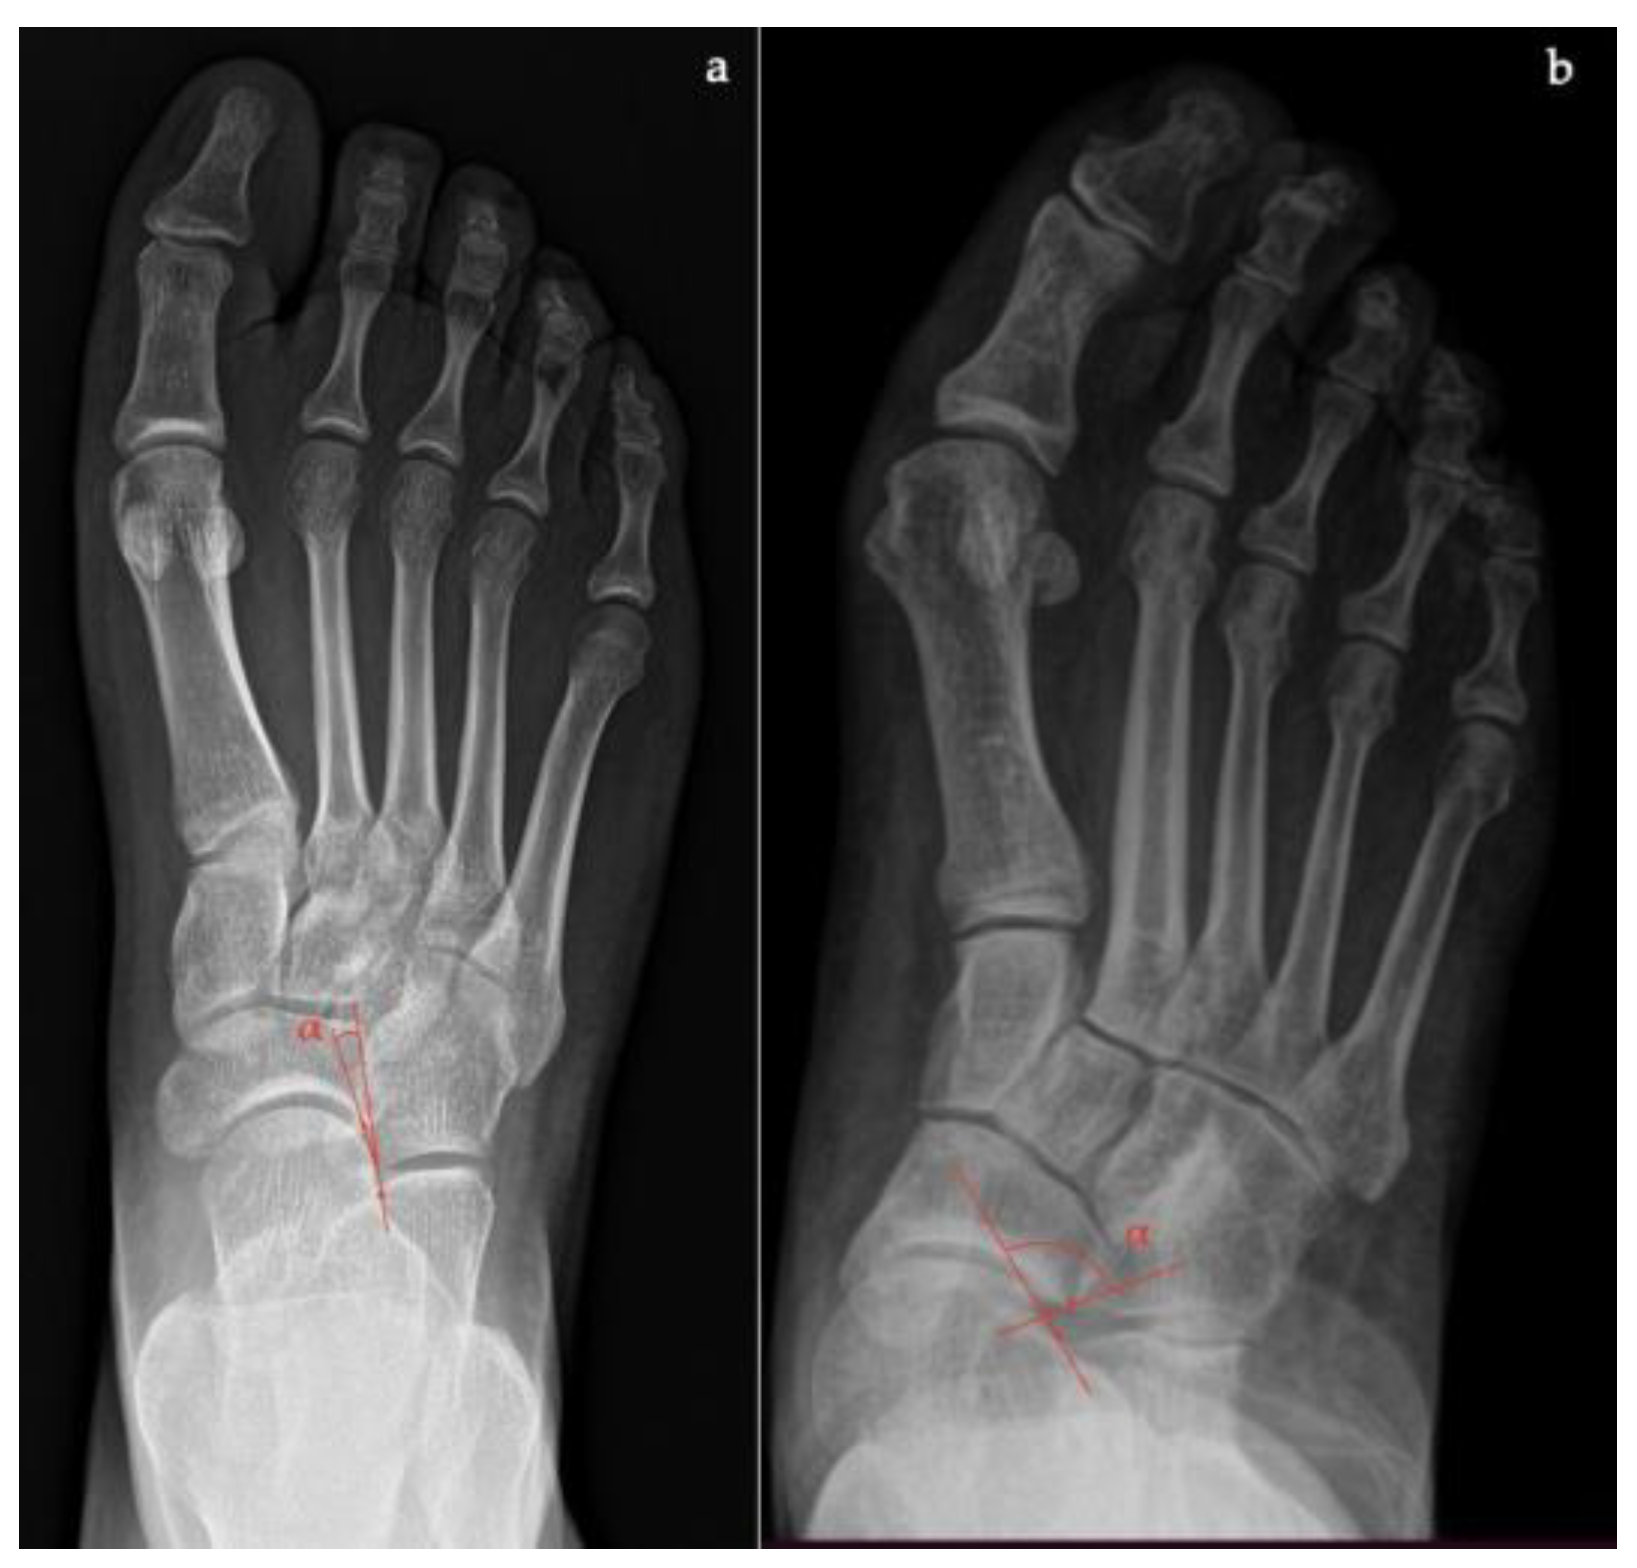

- Calcaneal-fifth metatarsal angle, defined as the angle formed between the tangent to the inferior aspect of the calcaneus and a line drawn along the inferior aspect of the base and head of the fifth metatarsal (normal <170°, flatfoot >170°) (Figure 8).